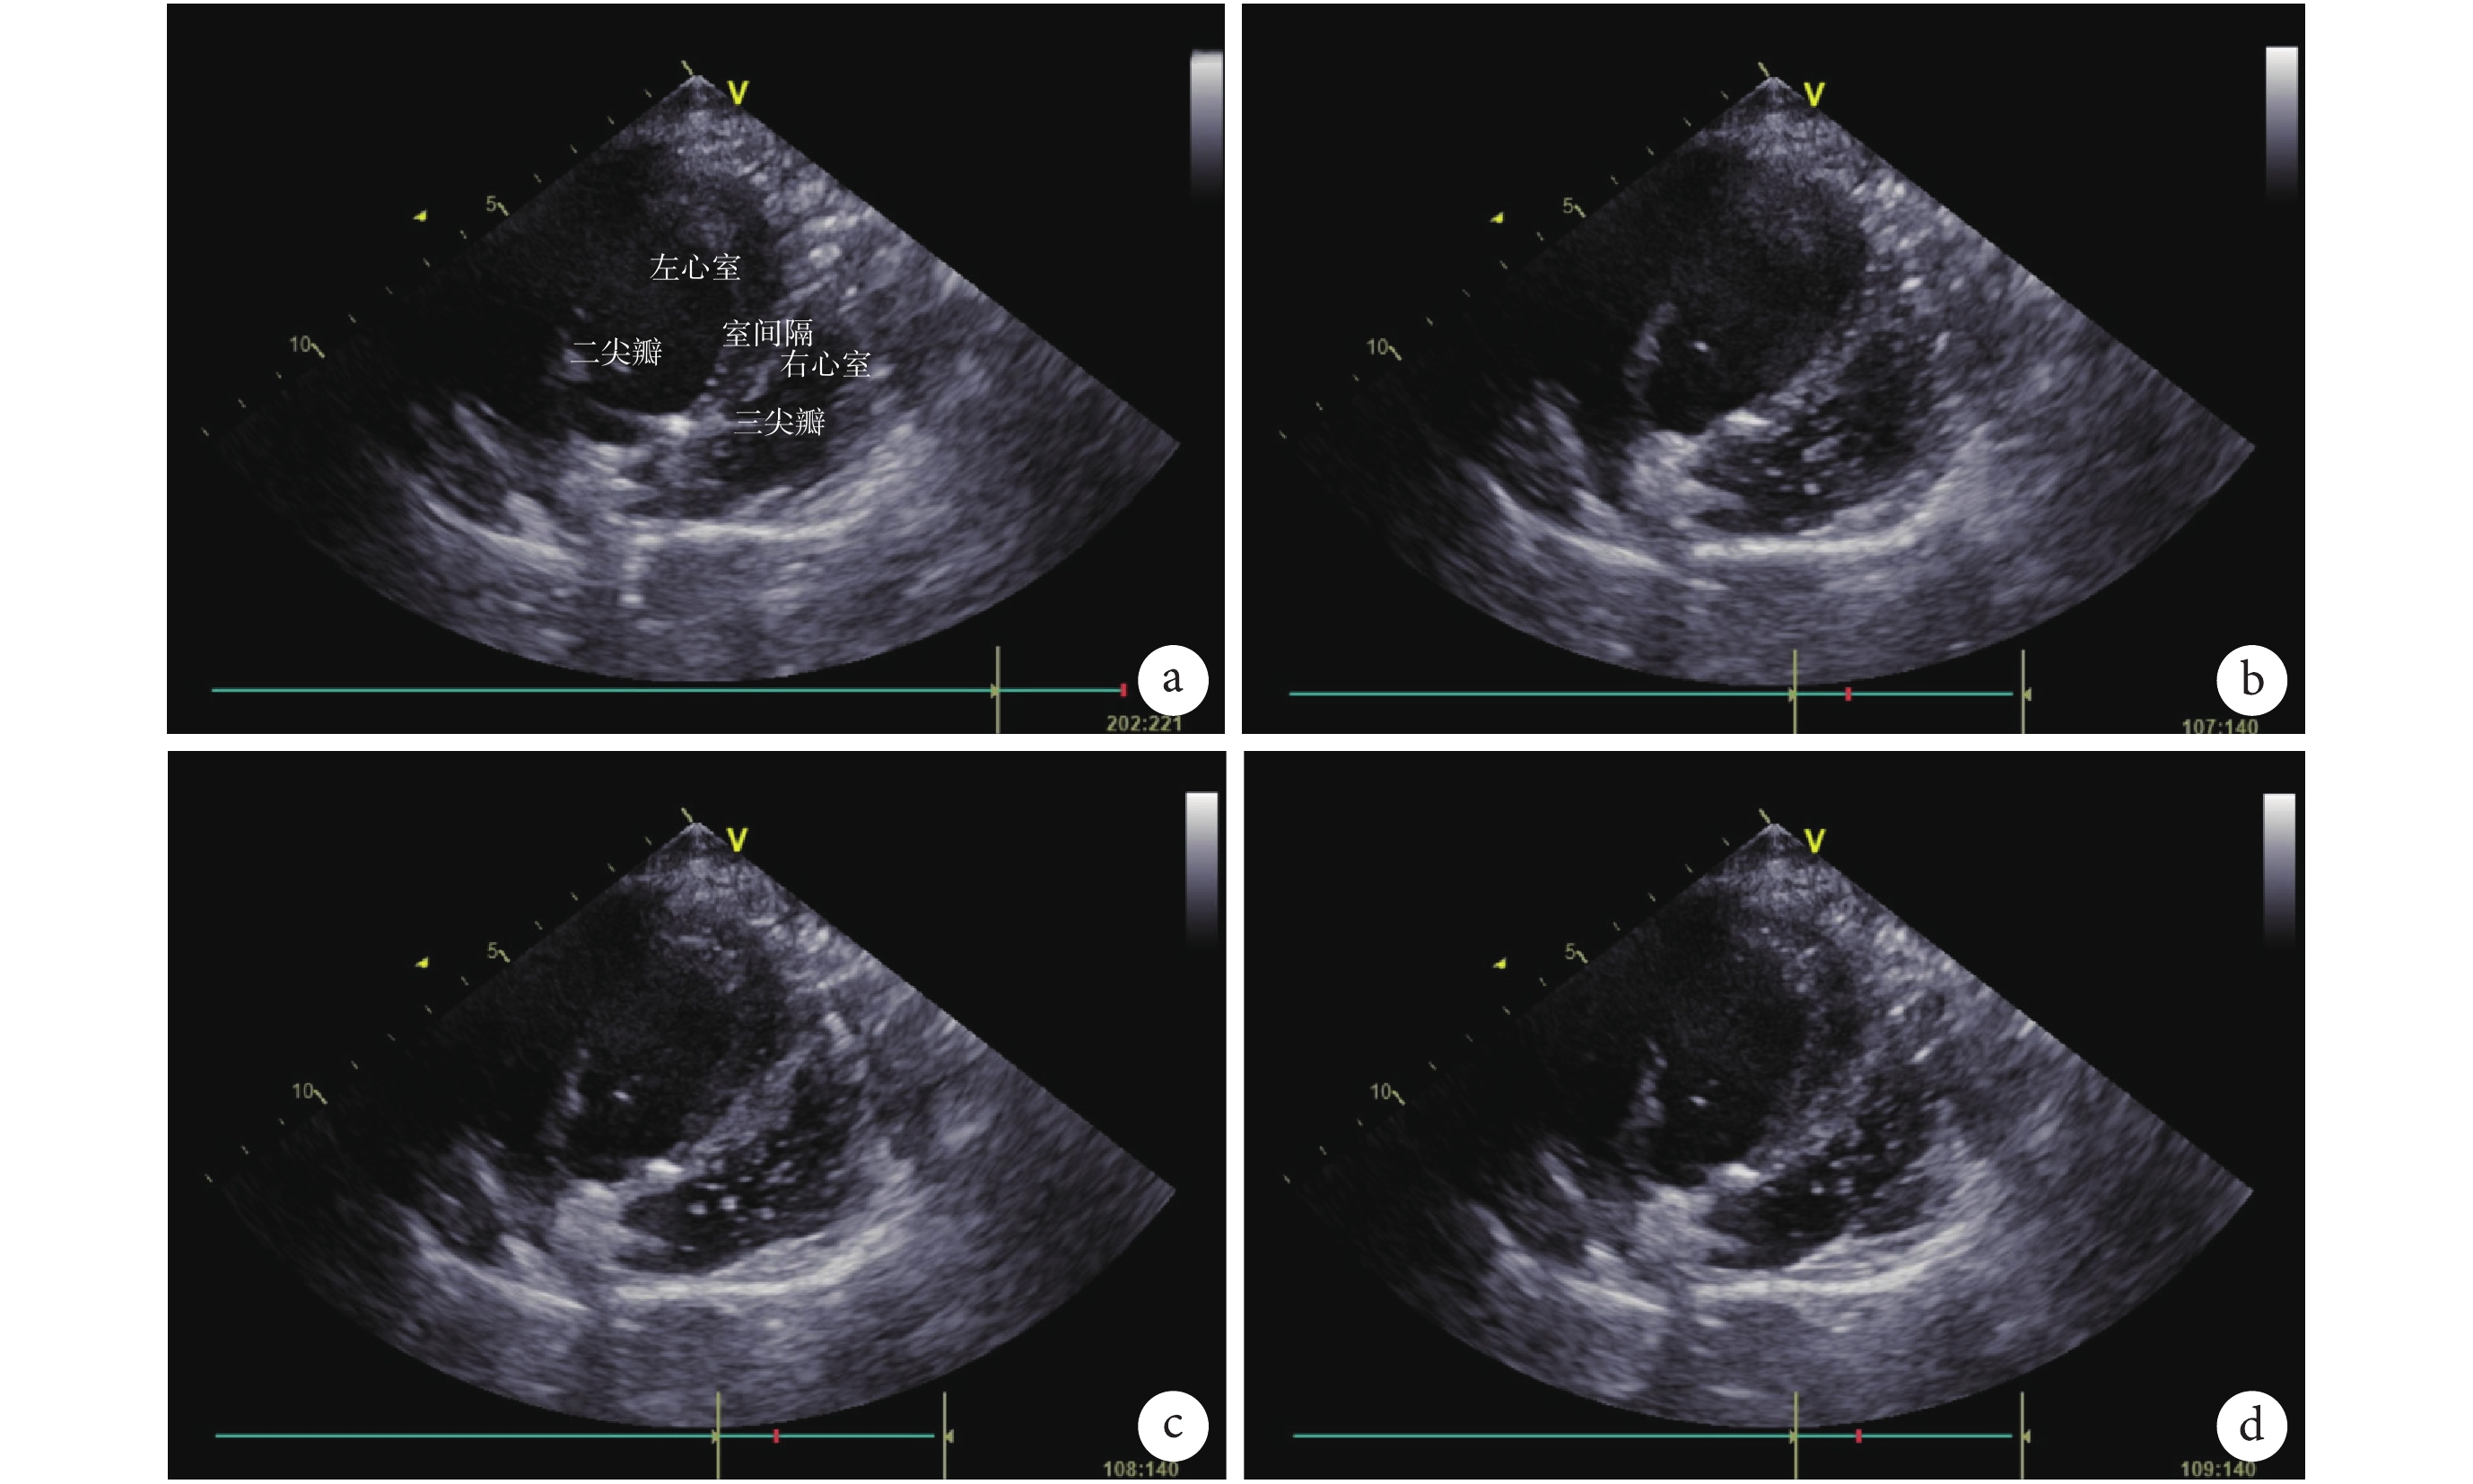

靜脈注射肝素 120 U/kg 進行全身抗凝。同時暴露右側頸靜脈,待活化凝血時間(activated clotting time,ACT)>200 s 后,經右側頸靜脈置入雙腔靜脈插管(Avalon Elite DLC,23Fr),導管尖端穿過右心房置入下腔靜脈(inferior vena cava,IVC)內;雙腔管回流口正對三尖瓣(超聲輔助判斷位置,圖 1)。ECMO 回路于外科操作前完成預充排氣,以上所有操作順利完成并確保無誤后將頸靜脈雙腔插管與 ECMO 回路的引流和回流端分別連接(圖 2a),連接過程中注意無菌操作,并避免系統進氣。連接完成后分別核對引流和回流管路,確認無誤后開始 ECMO 轉流。初始轉速為 3 000 轉/min,流量為 2 L/min。頸部切口連續縫合,牢固固定插管,管路繞頸部半周,避免移位和打折(圖 2b)。